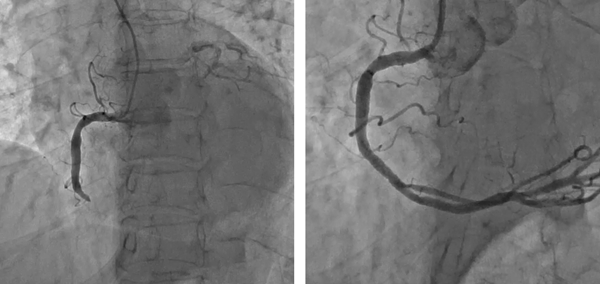

극심한 가슴 통증이 지속되면 최대한 빨리 관상동맥중재술이 가능한 병원으로 가야 한다. 급성심근경색으로 진단되면 막힌 혈관에 스텐트(금속 그물망)를 넣어 혈전으로 막힌 혈관을 뚫고 다시 피가 흐를 수 있도록 한다. 이렇게 스텐트로 막힌 관상동맥혈관을 뚫는 것이 관상동맥중재술이다. 급성심근경색으로 심장마비가 발생하면 4분 이내 심폐소생술과 함께 가능한 한 빨리 막힌 심장혈관을 뚫어야 한다. 심장동맥 폐쇄가 시작된 지 20분 이내에 심장 근육의 안쪽에서부터 괴사가 시작돼 2~4시간 후에는 바깥쪽까지 진행해 심장 근육 전체가 손상된다. 대개 발병 직후 병원에 도착하기 전에 약 30%가 사망하며, 병원에 도착해서 적극적인 치료를 하더라도 사망률이 5~10% 이른다.

이관용 교수는 “과거에는 심근경색증을 치료하기 위해 혈전 용해제를 많이 사용했지만 일부 환자에선 효과가 적고, 고위험 환자에서는 뇌출혈의 위험성이 있으며, 혈전이 뚫리더라도 시간이 오래 걸려 치료 효과가 떨어졌다며 최근엔 말초 혈관을 통한 시술인 관상동맥중재술을 주로 시행한다”고 말했다.